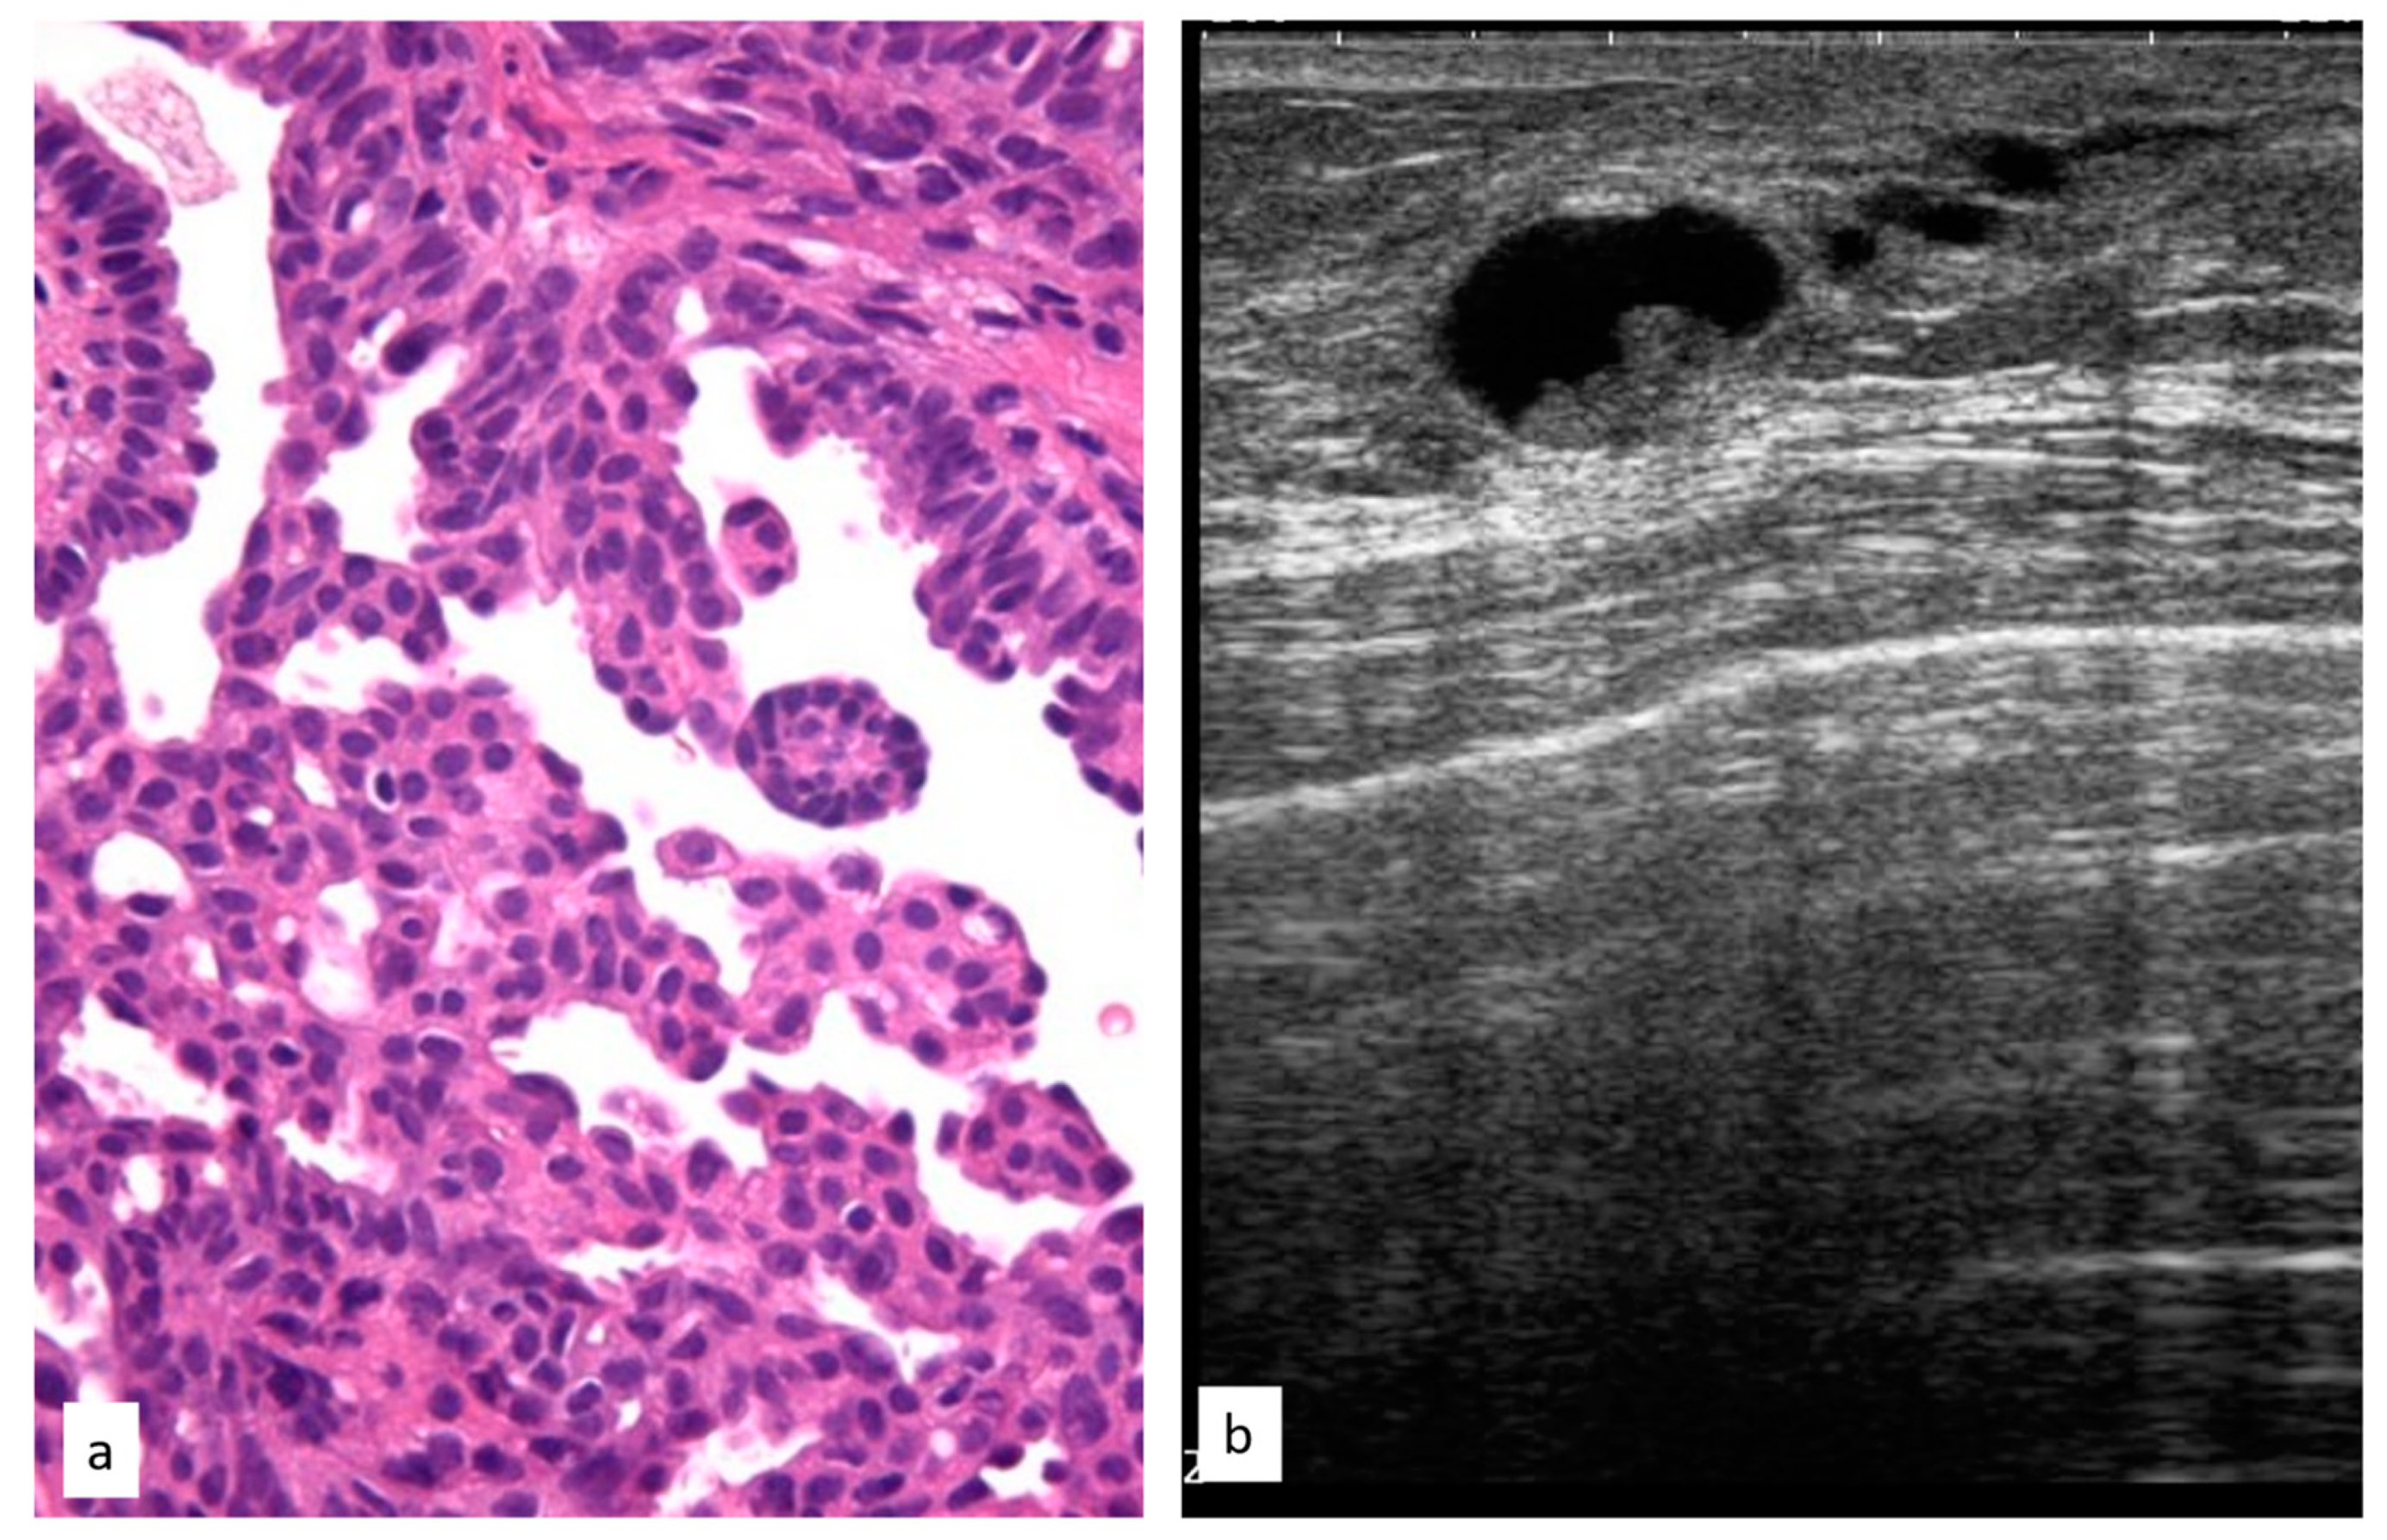

3.3.4. Atypical Papillary Lesion